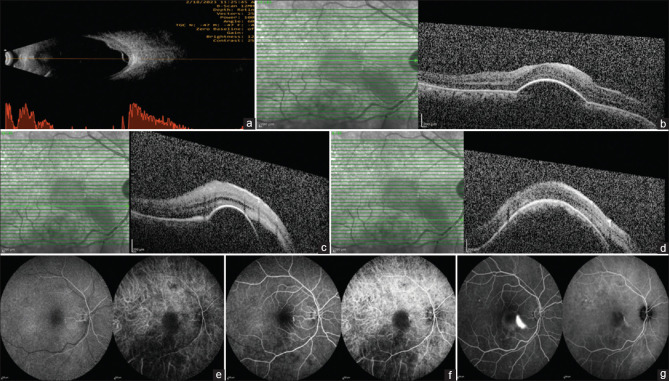

中枢性浆液性脉络膜视网膜病变(CSCR)的发生是由于脉络膜毛细血管的高渗透性,与视网膜色素上皮(RPE)功能障碍一起,导致浆液性神经感觉视网膜脱离。限定脉络膜血管瘤也以黄斑浆液性神经感觉脱离为特征,引起RPE退行性改变,很少模仿CSCR。在此,我们报告一例中年患者的CSCR,表现为脉络膜肿块病变,表现为孤立的脉络膜升高,视网膜下有液体和脉络膜后积液,在眼底荧光血管造影引导的病灶激光后显示液体完全溶解。

Central serous chorioretinopathy (CSCR) occurs due to hyper-permeable choroidal capillaries, which, along with retinal pigment epithelium (RPE) dysfunction, causes a serous neurosensory retinal detachment. Circumscribed choroidal hemangiomas are also characterized by serous neurosensory detachment of the macula and cause degenerative changes to the RPE, rarely mimicking CSCR. Here, we present a case of CSCR in a middle-aged patient mimicking as a choroidal mass lesion who presented as a solitary choroidal elevation with subretinal fluid and posterior choroidal loculation of fluid and showed complete resolution of fluid after fundus fluorescence angiography-guided focal laser.